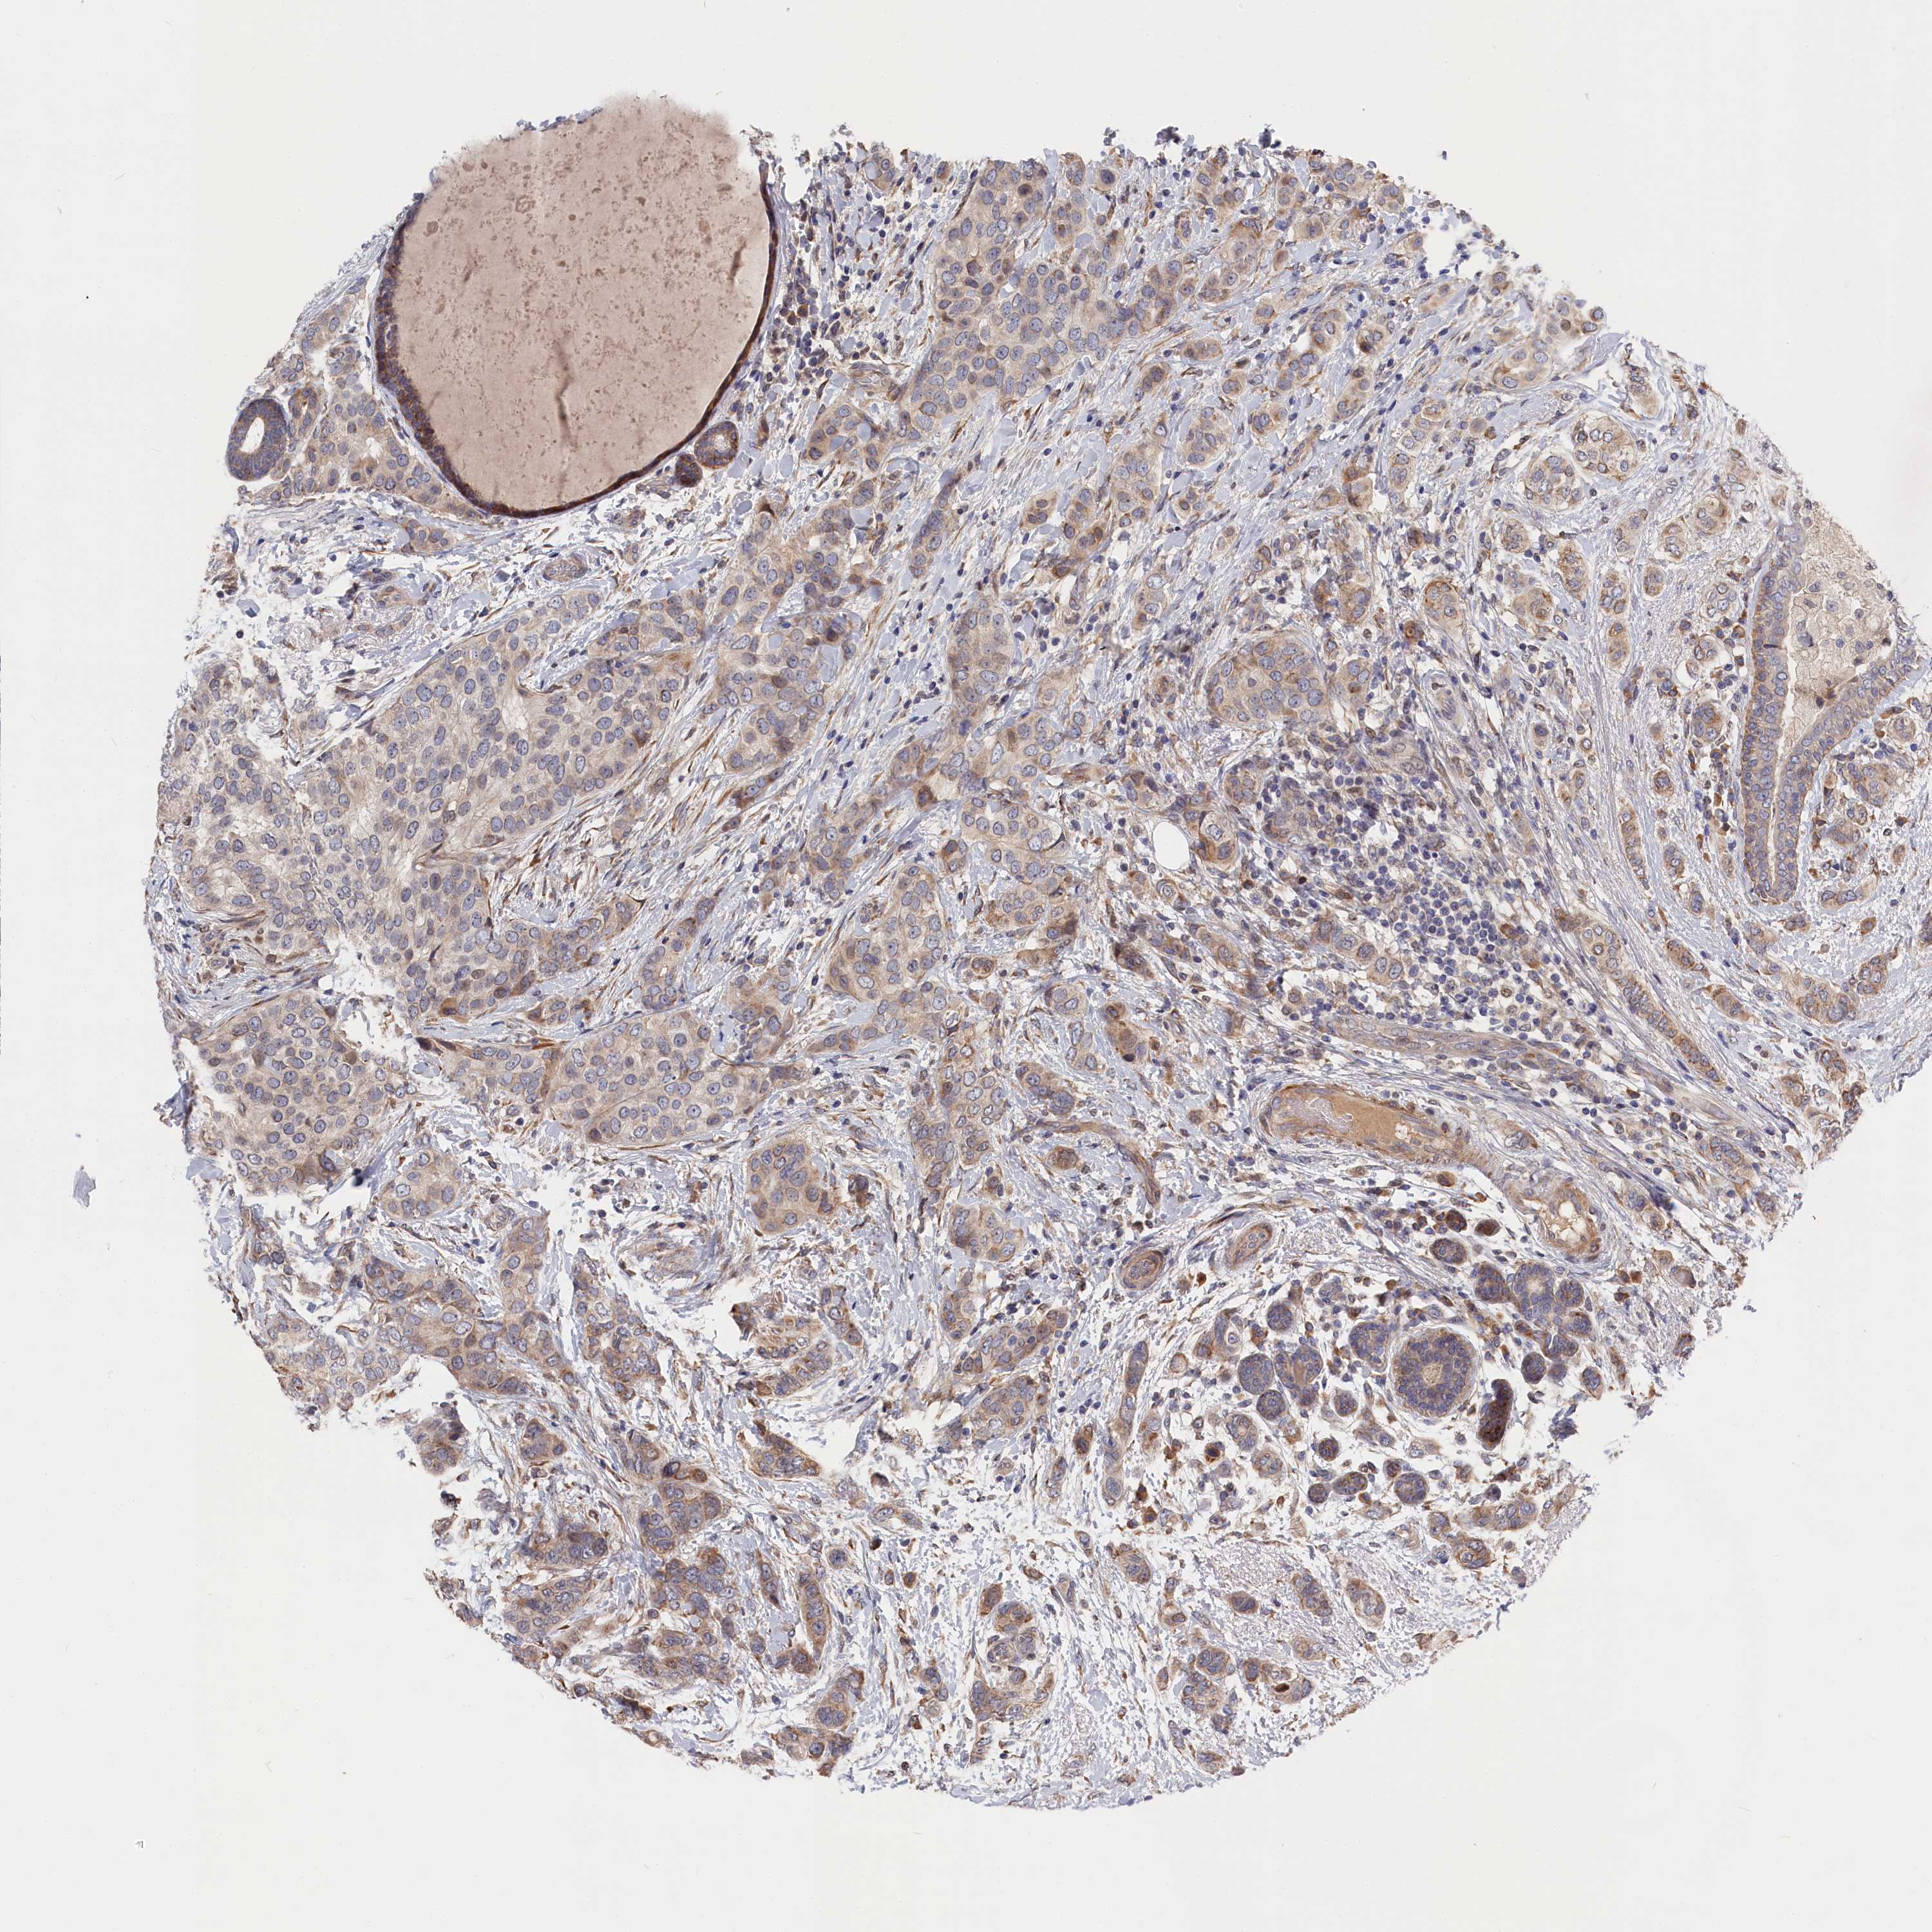

CANCER BREAST CANCER Show tissue menu

BRCA TCGA BRCA VALIDATION PROTEIN EXPRESSION